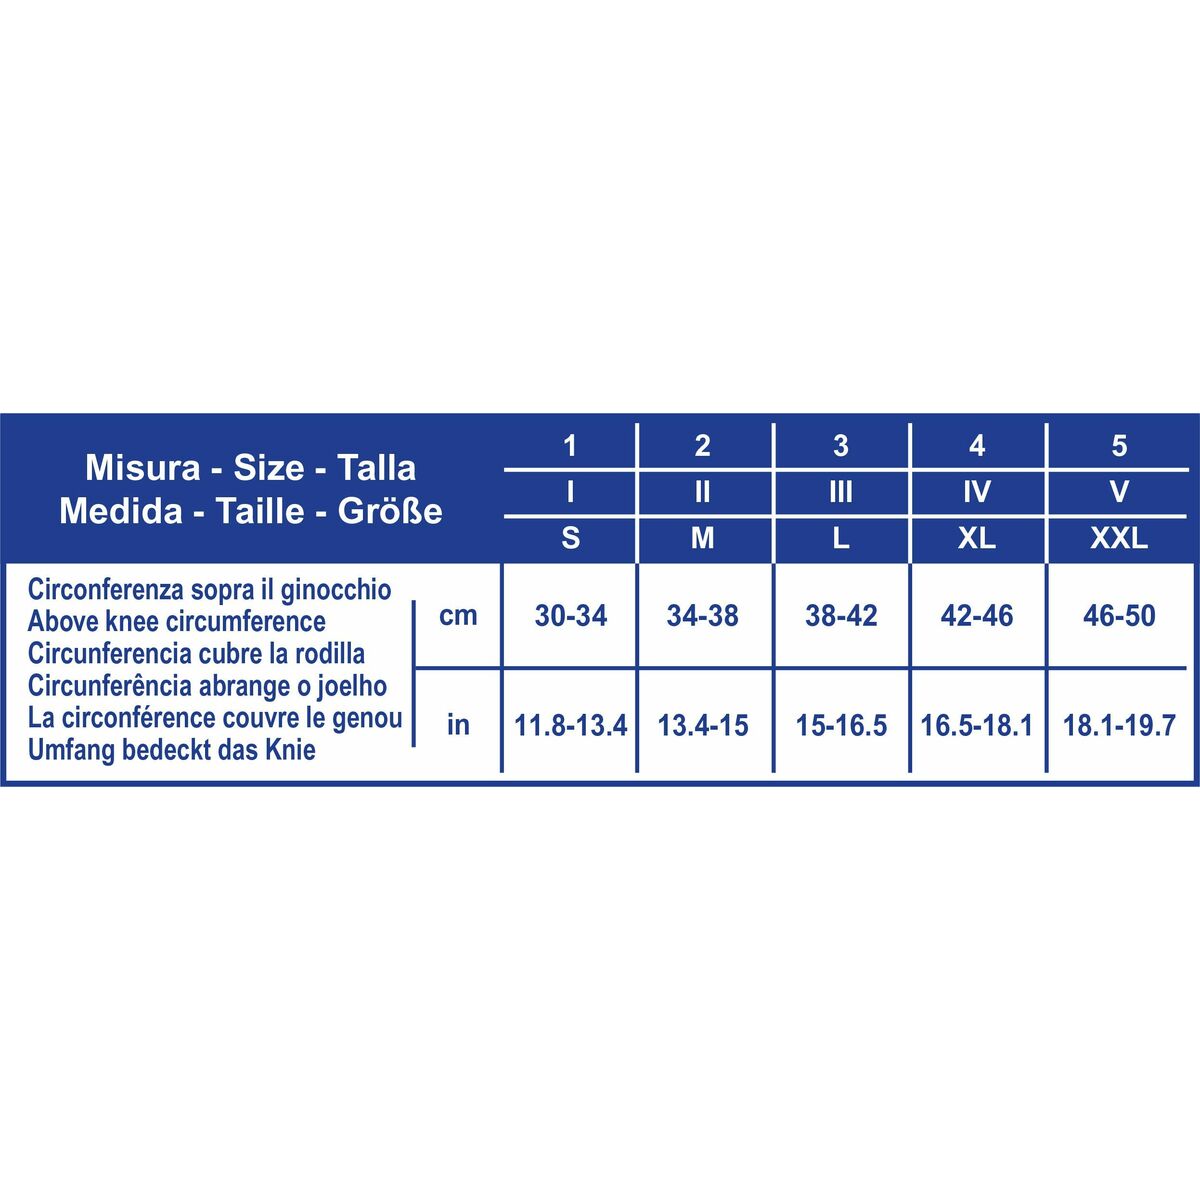

Če iščete novosti ki so hit na trgu, vam predstavljamo Kolenski Ščitnik (Prenovljeni izdelki A+)!

- Barva: Meso